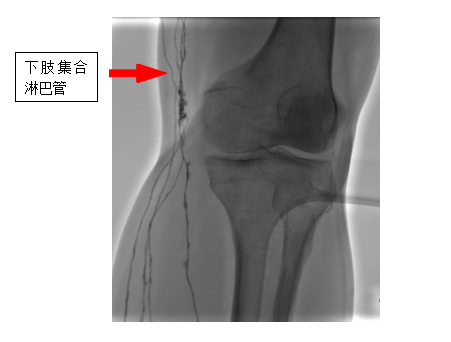

直接淋巴系統造影是一種先進的醫學影像技術與手術的融合技術,它通過超顯微技術將特殊的造影劑注入淋巴系統,在數字減影設備下使淋巴管及淋巴結清晰顯影,從而能夠精確診斷淋巴系統的回流障礙、漏出、返流、畸形等疾病,對于淋巴管瘤、淋巴水腫、乳糜漏、淋巴結轉移癌等疾病的診斷和治療具有重要意義。